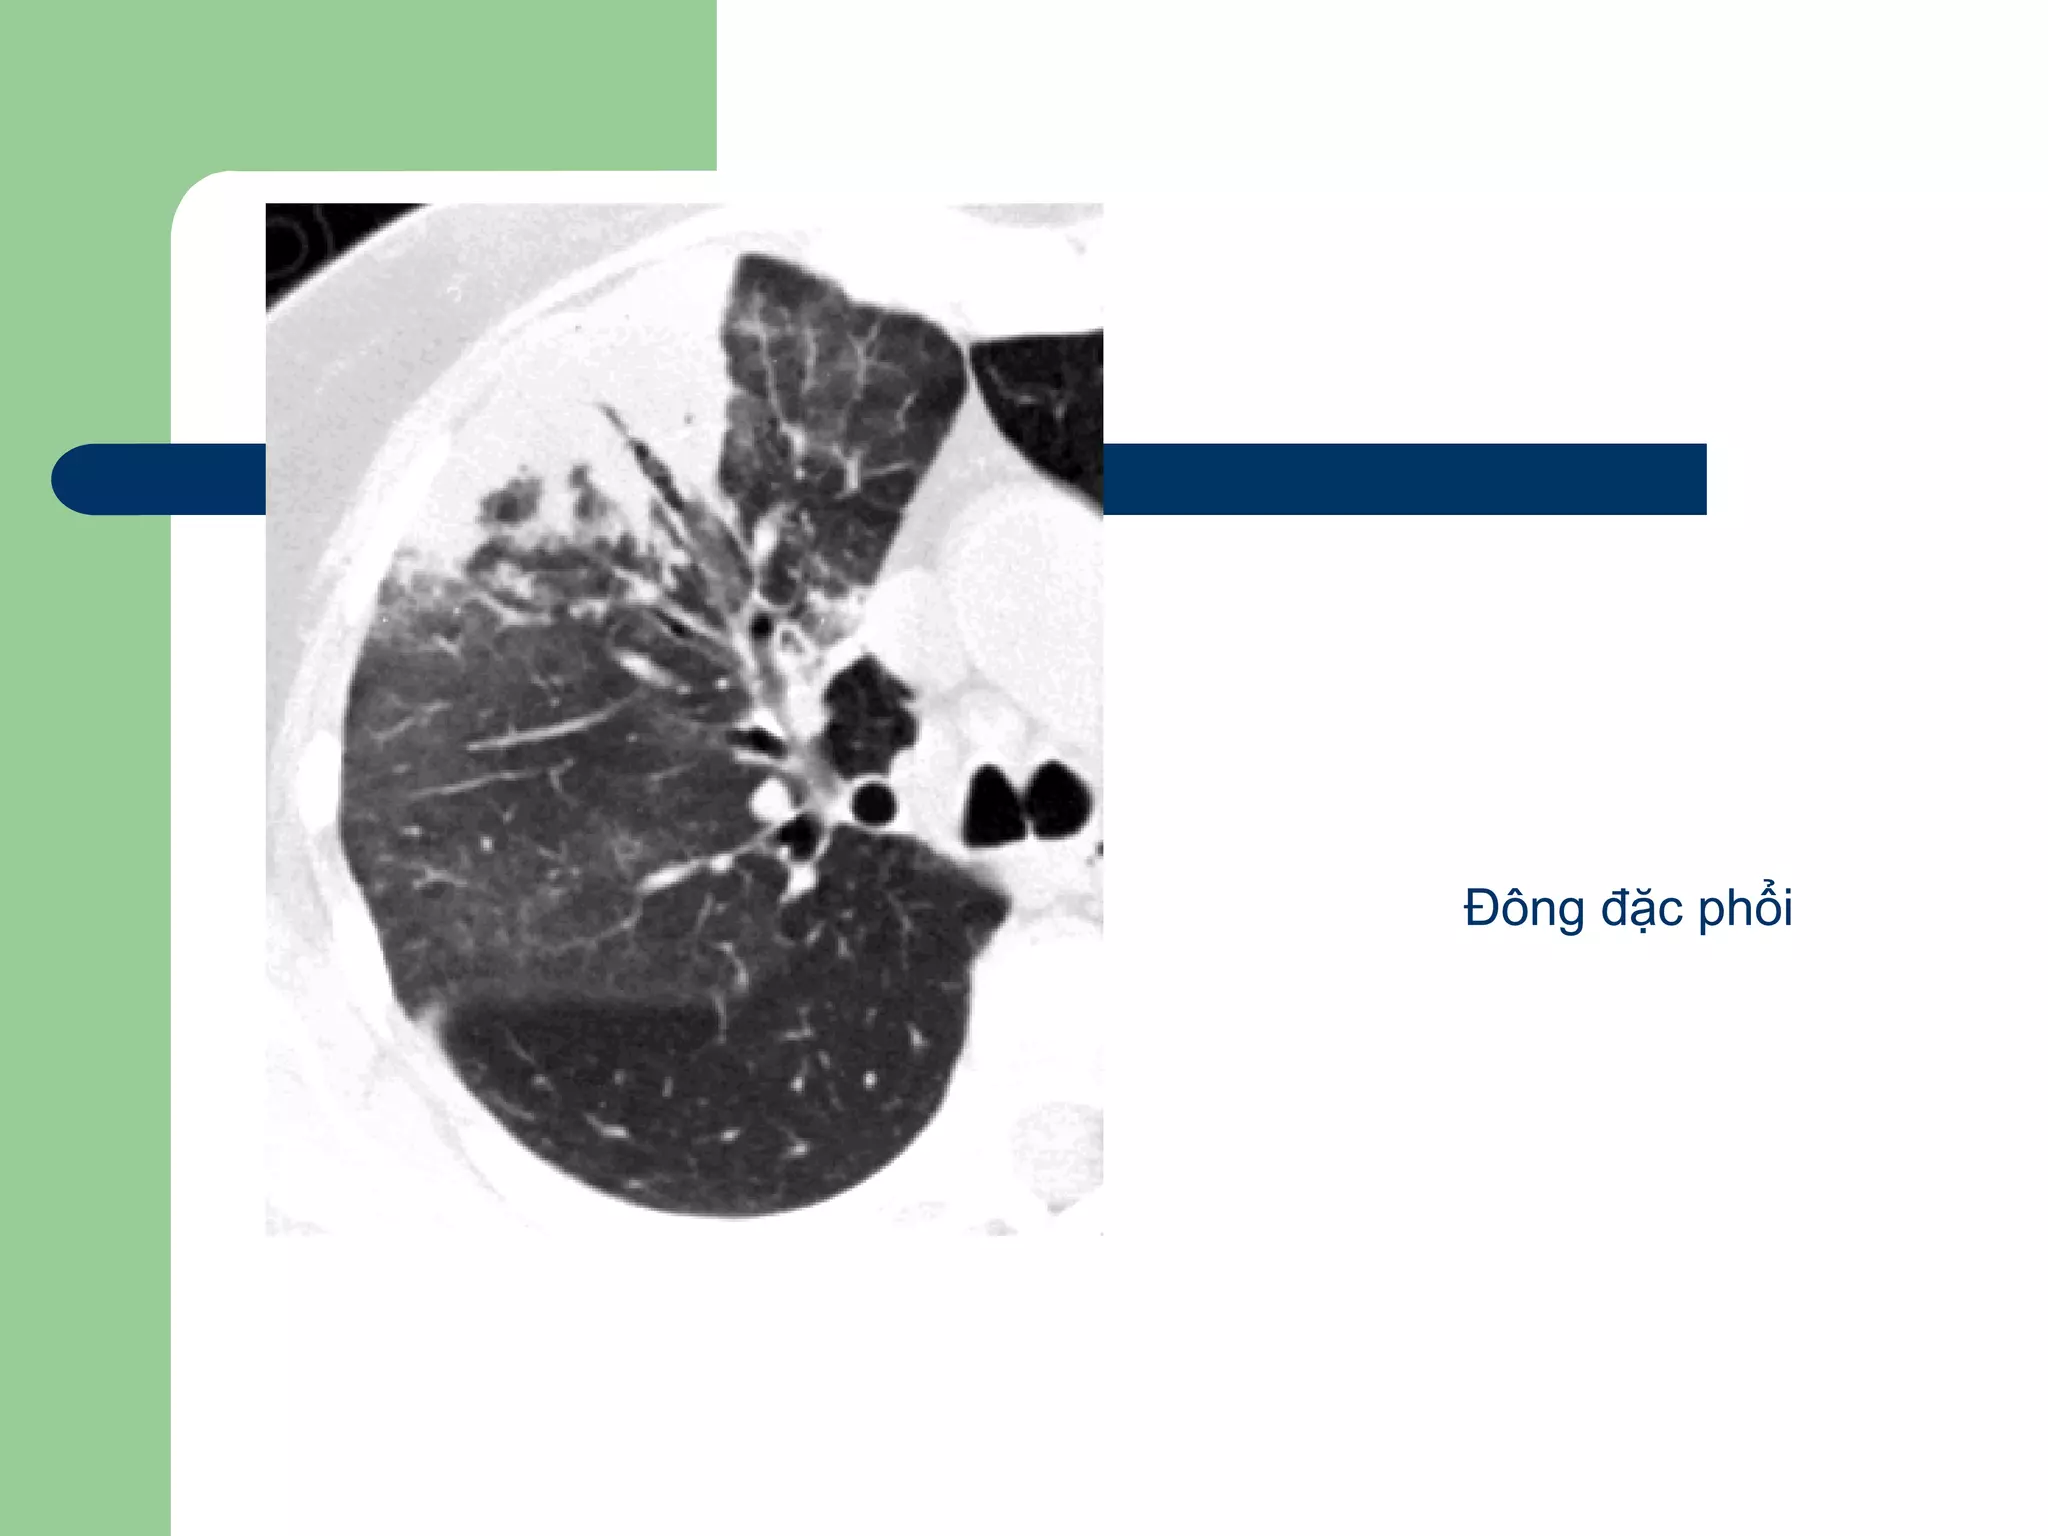

 Viêm phổi thùy

– Do phế cầu

– Thường bắt đầu ở khoảng khí đọan

xa, tạo các vùng đông đặc, tiến trỉên

tòan bộ phổi

– CT: các bóng mờ đồng nhất nhiều

phân thùy hoặc tòan bộ thùy phổi

dấu hiệu ‘khí phế quản đồ’

Đông đặc phổi